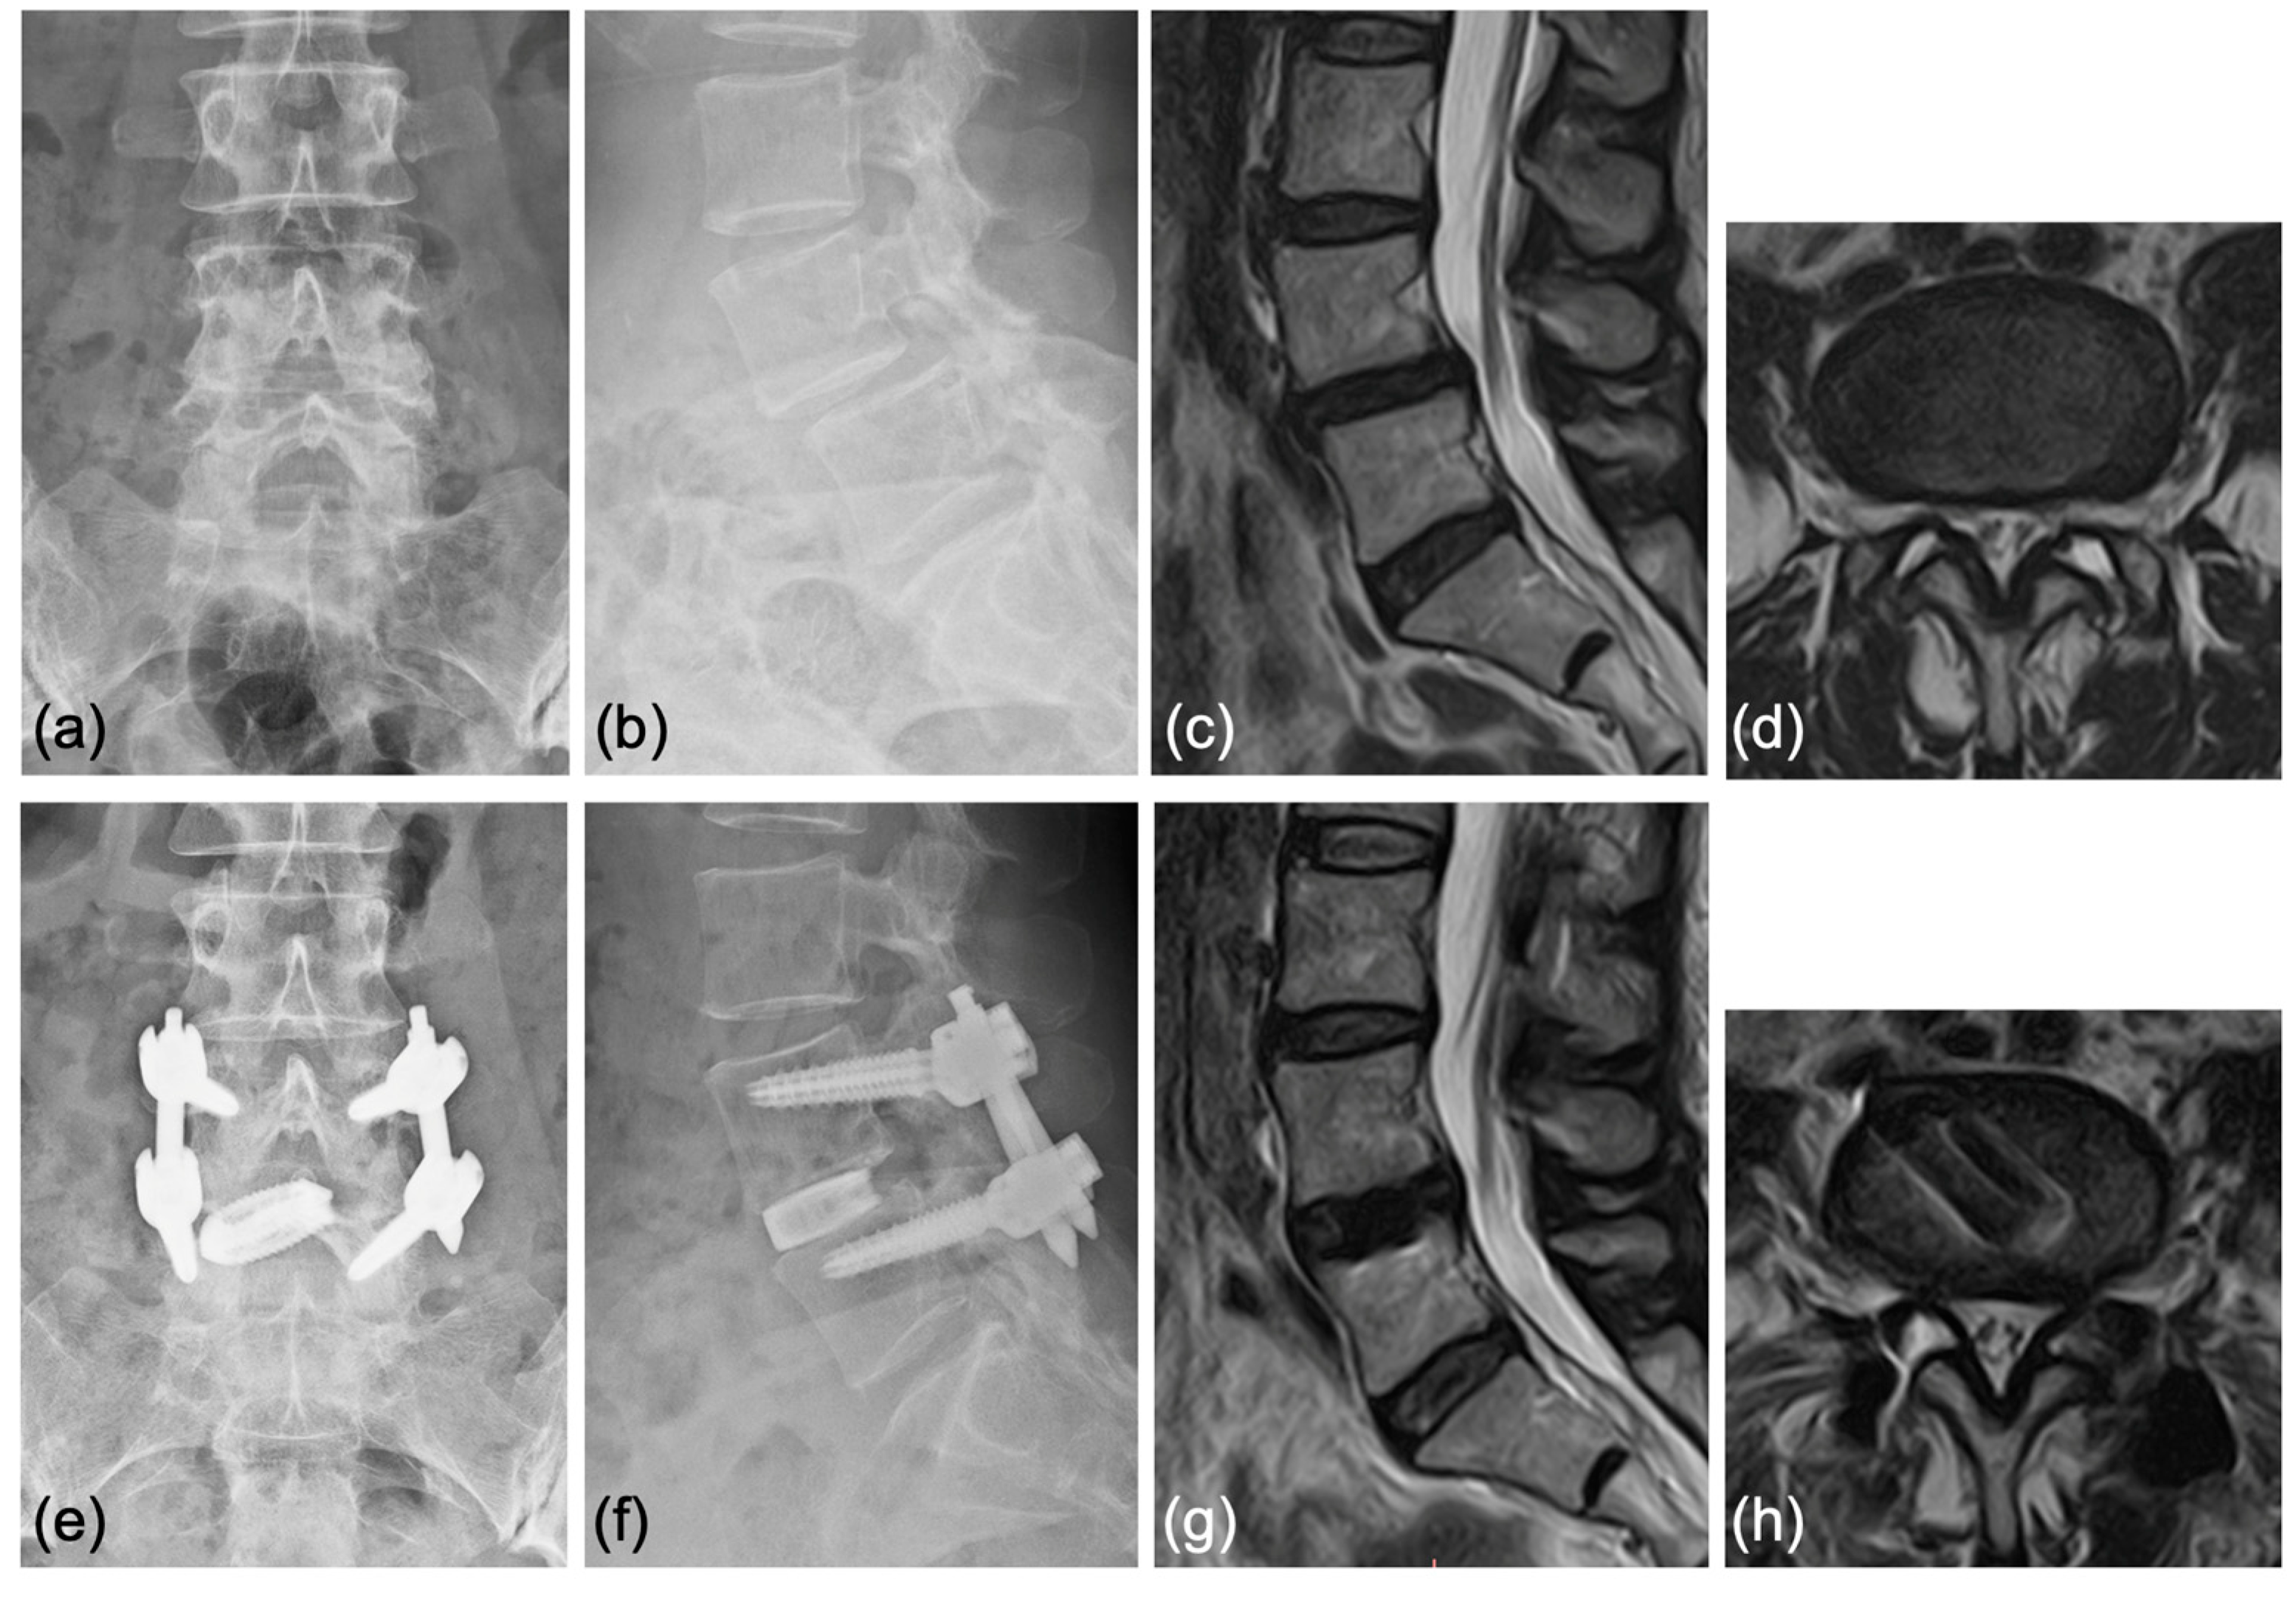

Case 1: A 70-year-old woman was diagnosed with degenerative spondylolisthesis of the L4 vertebra with instability by X-ray, CT, and MRI. VAS for back and leg pain were 100 and 60 mm, and the JOA score was 18/29. The spinal canal area was 95 mm2 at L4/5 disc level, and the % slip was 21% (Figure 7a–d). After the failure of conservative treatment, PETLIF was performed. One month after surgery, VAS back and leg pain improved significantly to 0 and 10 mm. Postoperative X-ray and MRI showed that the % slip was 0%, and the spinal canal area was expanded to 153 mm2 (Figure 7e–h). Bone fusion of L4/5 was confirmed by X-ray and CT scan one year after the surgery (Figure 8a–d).

Figure 8.

Bony fusion through the titanium cage was confirmed by (a,b) anterior and posterior flexed lateral X-rays and (c,d) sagittal and coronal CT scans.